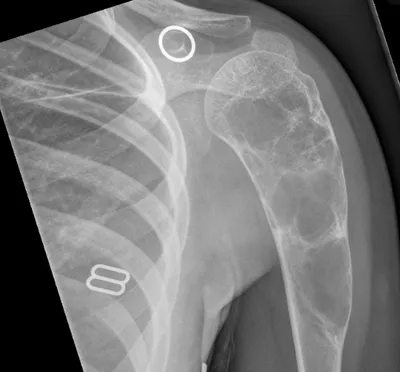

Humerus Radiology Images

This collection contains 1 radiology images related to humerus, including various imaging modalities such as X-rays, MRIs, CT scans, and ultrasound images commonly used in medical diagnosis and education.